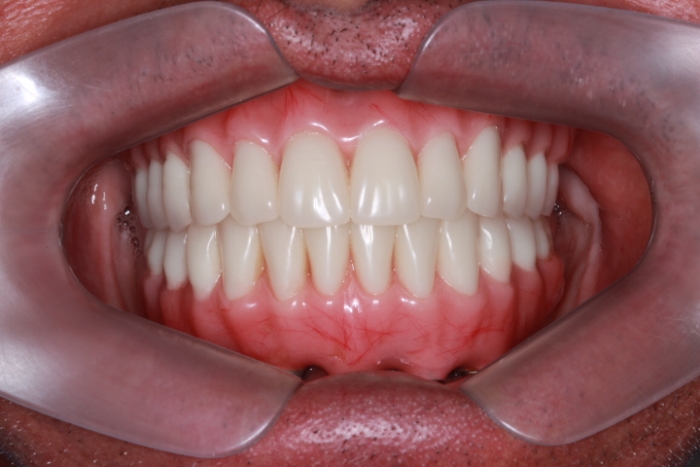

Prótese fixa sobre os implantes inferiores e nova prótese total superior, em Janeiro de 2016

Sorriso Final, em 2016